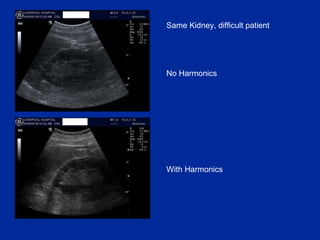

Same Kidney, difficult patient No Harmonics With Harmonics

Harmonics (THI) As a sound wave travels through tissue, the high pressure bit (compressing tissue) moves  faster  than the rarefactional component.  This  distorts  the wave! and generates higher frequency components ( harmonics ) deep in the tissues. eg 3MHz wave creates 6MHz, 12 MHz harmonics

Harmonics (THI) Q: So what? A: it turns out that aberrant/artefact signals are too  weak  to generate harmonic waves. THI takes advantage of this: i.e. it displays  only  the harmonic signals. THI images have: reduced noise and clutter improved spatial resolution (harmonic beams are narrower than the original)

Top tip:  Harmonics (THI) = another great button Don ’t use it for the lung For other regions, give it a go If it makes the image worse, press again to turn it off Best for  mid-depth  images. harmonic generation does not take place near the skin, so THI no use there.  Also less useful in far field.